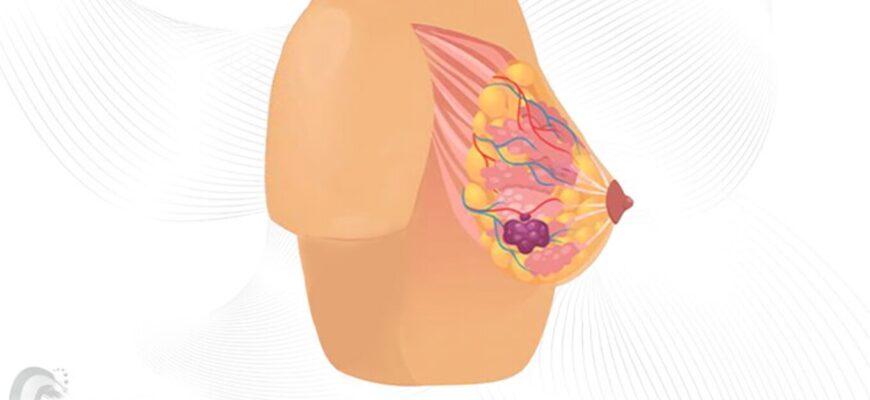

Поширені причини болю в правому боці

- Апендицит

- Запалення жовчного міхура

- Проблеми з печінкою

Апендицит: коли варто насторожитись?

Можливо, апендицит – це одне із перших захворювань, яке спадає на думку при виникненні болю в правому боці. Це запалення апендикса, яке, якщо не лікувати, може призвести до серйозних ускладнень.

Інші можливі причини болю

А що як не апендицит? Біль в правому боці може бути пов’язаний з проблемами у жовчному міхурі. Запалення, яке провокує жовчні камені та інші неполадки, зазвичай супроводжується гострим болем, що поширюється на спину або плечі.

Ще однією поширеною причиною є проблеми з печінкою. Це може бути пов’язано з інфекцією, алкоголем або жировим гепатозом. А ще це ледь не забутий виняток: м’язове напруження. Ми так звикли до життя у стресі, що часто забуваємо про те, як це впливає на наш організм.